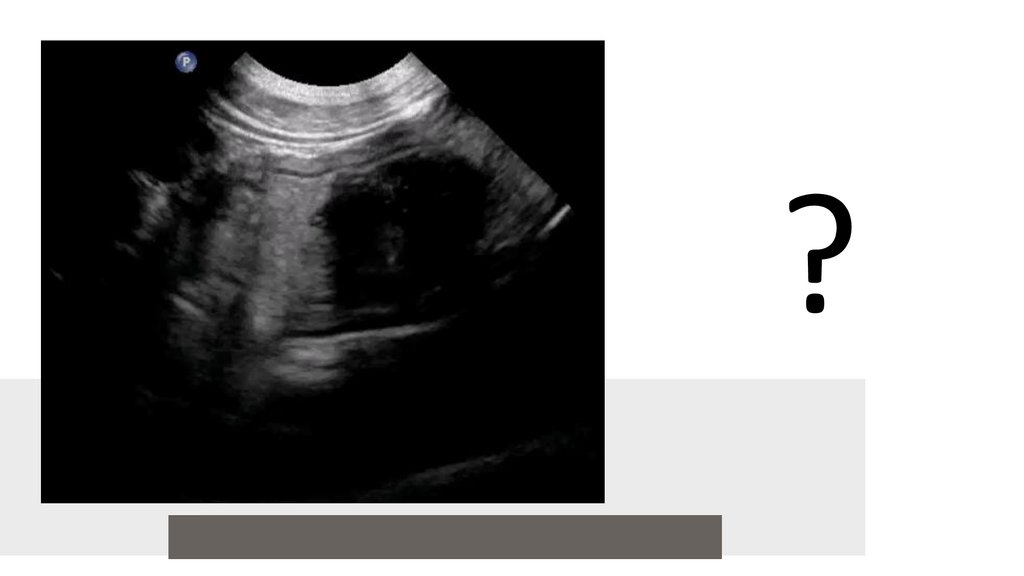

?